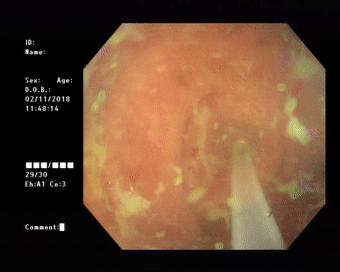

患者做好肠道准备后于30日上午在内镜室进行了内镜下逆行阑尾炎治疗术。电子结肠镜到达回盲部, 进入盲肠,可见:阑尾开口呈半月形,边缘粘膜充血、水肿,诊断考虑“急性阑尾炎”。随后,在斑马导丝引导下将取导管引导入阑尾腔用生理盐水进行阑尾腔反复冲洗可见乳白色脓液涌出,见脓液流尽用,并用替硝唑保留阑尾灌注,退镜,患者自诉腹痛明显缓解。

(镜下可见)